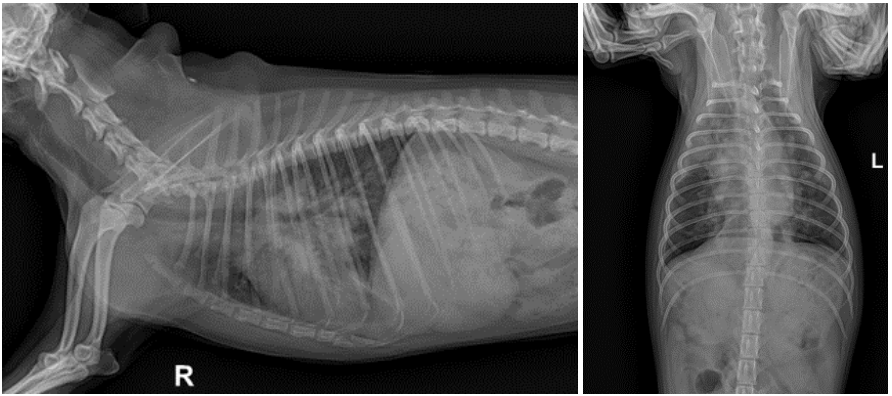

흉부방사선 상에서 폐전엽에 걸친 침윤이 있었으며 복배상에서는 결절로 의심되는 부분도 확인되었습니다. ▼

CT검사 상에서 폐엽 전체에 걸친 침윤을 확인하였으며 일부엽에서는 조영증강을 동반한 결절도 확인되었습니다.